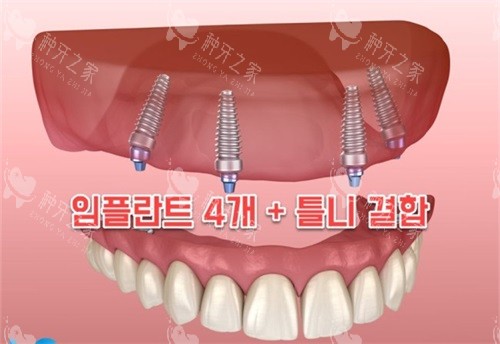

三、多样化的产品系列

奥齿泰种植系统提供了多种型号的种植体,如TSIII超短种植体、TSIV种植体等,以满足不同患者的种植需求。这些种植体适用于各种复杂的口腔情况,如牙槽骨吸收、疏松骨质等。多样化的产品系列不仅为患者提供了更多的选择,也提高了种植的成功概率和稳定性。